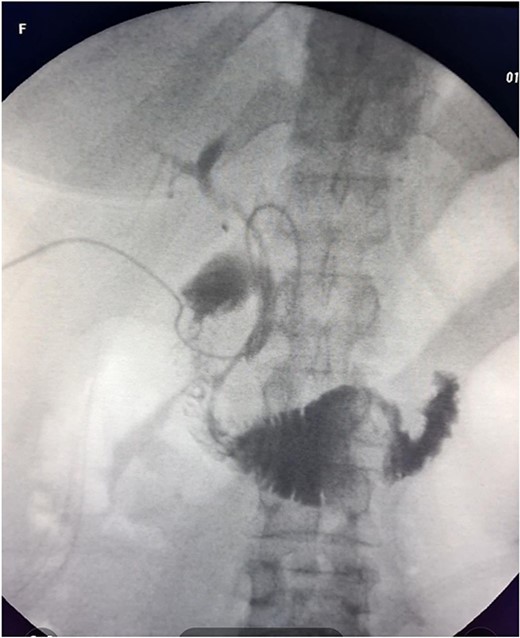

The patient was scheduled for a laparoscopic cholecystectomy the following day. Intraoperatively, an enlarged gallbladder hydrops with the presence of various caliber calculi in the lumen, the largest of which measured 2 cm/d, was found. The contents of the bladder are punctured and evacuated to facilitate its grasping in the fundus area and creating a good exposure of Callot’s triangle. Using a four trocar technique, a dissection was performed in the triangle of Callot, noting the difficult manipulation in the area between cystic duct and common hepatic duct. The cystic duct is identified to its confluence with the common bile duct at a 45° angle. The cystic artery was also visualized, after which clips were placed on both structures after ensuring that they entered the gallbladder. Dissection of the gallbladder in its distal part, attached to the liver parenchyma above Rouvier’s line, was started using electrocautery and hook. The tissue density of a limited area in the distal part between the wall of the gallbladder and the liver parenchyma was dissected using a hook. A bile duct was opened in its unusual anatomical location (Fig. 1). Due to lack of equipment for intraoperative cholangiography, it was converted to open access and subsequent revision of the extrahepatic bile ducts. The common bile duct and right–left hepatic duct were mobilized to the site of entry into the liver parenchyma. A parietal lesion of the right hepatic duct just above the confluence and anatomical integrity of the common bile duct and left hepatic duct were found. After examining the removed gallbladder, it was found that it was immediately flowing into a duct which connects the cystic duct with the right hepatic duct as depicted in Fig. 2. A plasty of the right hepatic duct was performed, and prior to this duodenotomy and papillotomy were performed by mobilization of the duodenum according to Kocher. A protective drain was placed in the choledochus draining from the right hepatic duct to the ampulla of Vater. Separetely, the clips previously placed on the cystic duct were removed and a transcystic drain was placed; a leak test was performed at the plastic site of the right hepatic duct. The postoperative period was without complications. From the transcystic drain, the secretion of bile stopped on the fourth postoperative day. On the eighth postoperative day, transdrainage cholangiography was performed; the common bile duct and bought hepatic ducts were imaged, and free passage of the contrast material through the duodenum was established (Fig. 3). The transcystic draine was removed on the 20th day of surgery.

Visualization of the biliary lesion; (1) tangential damage to the right hepatic duct; (2) gallbladder with lateral traction.